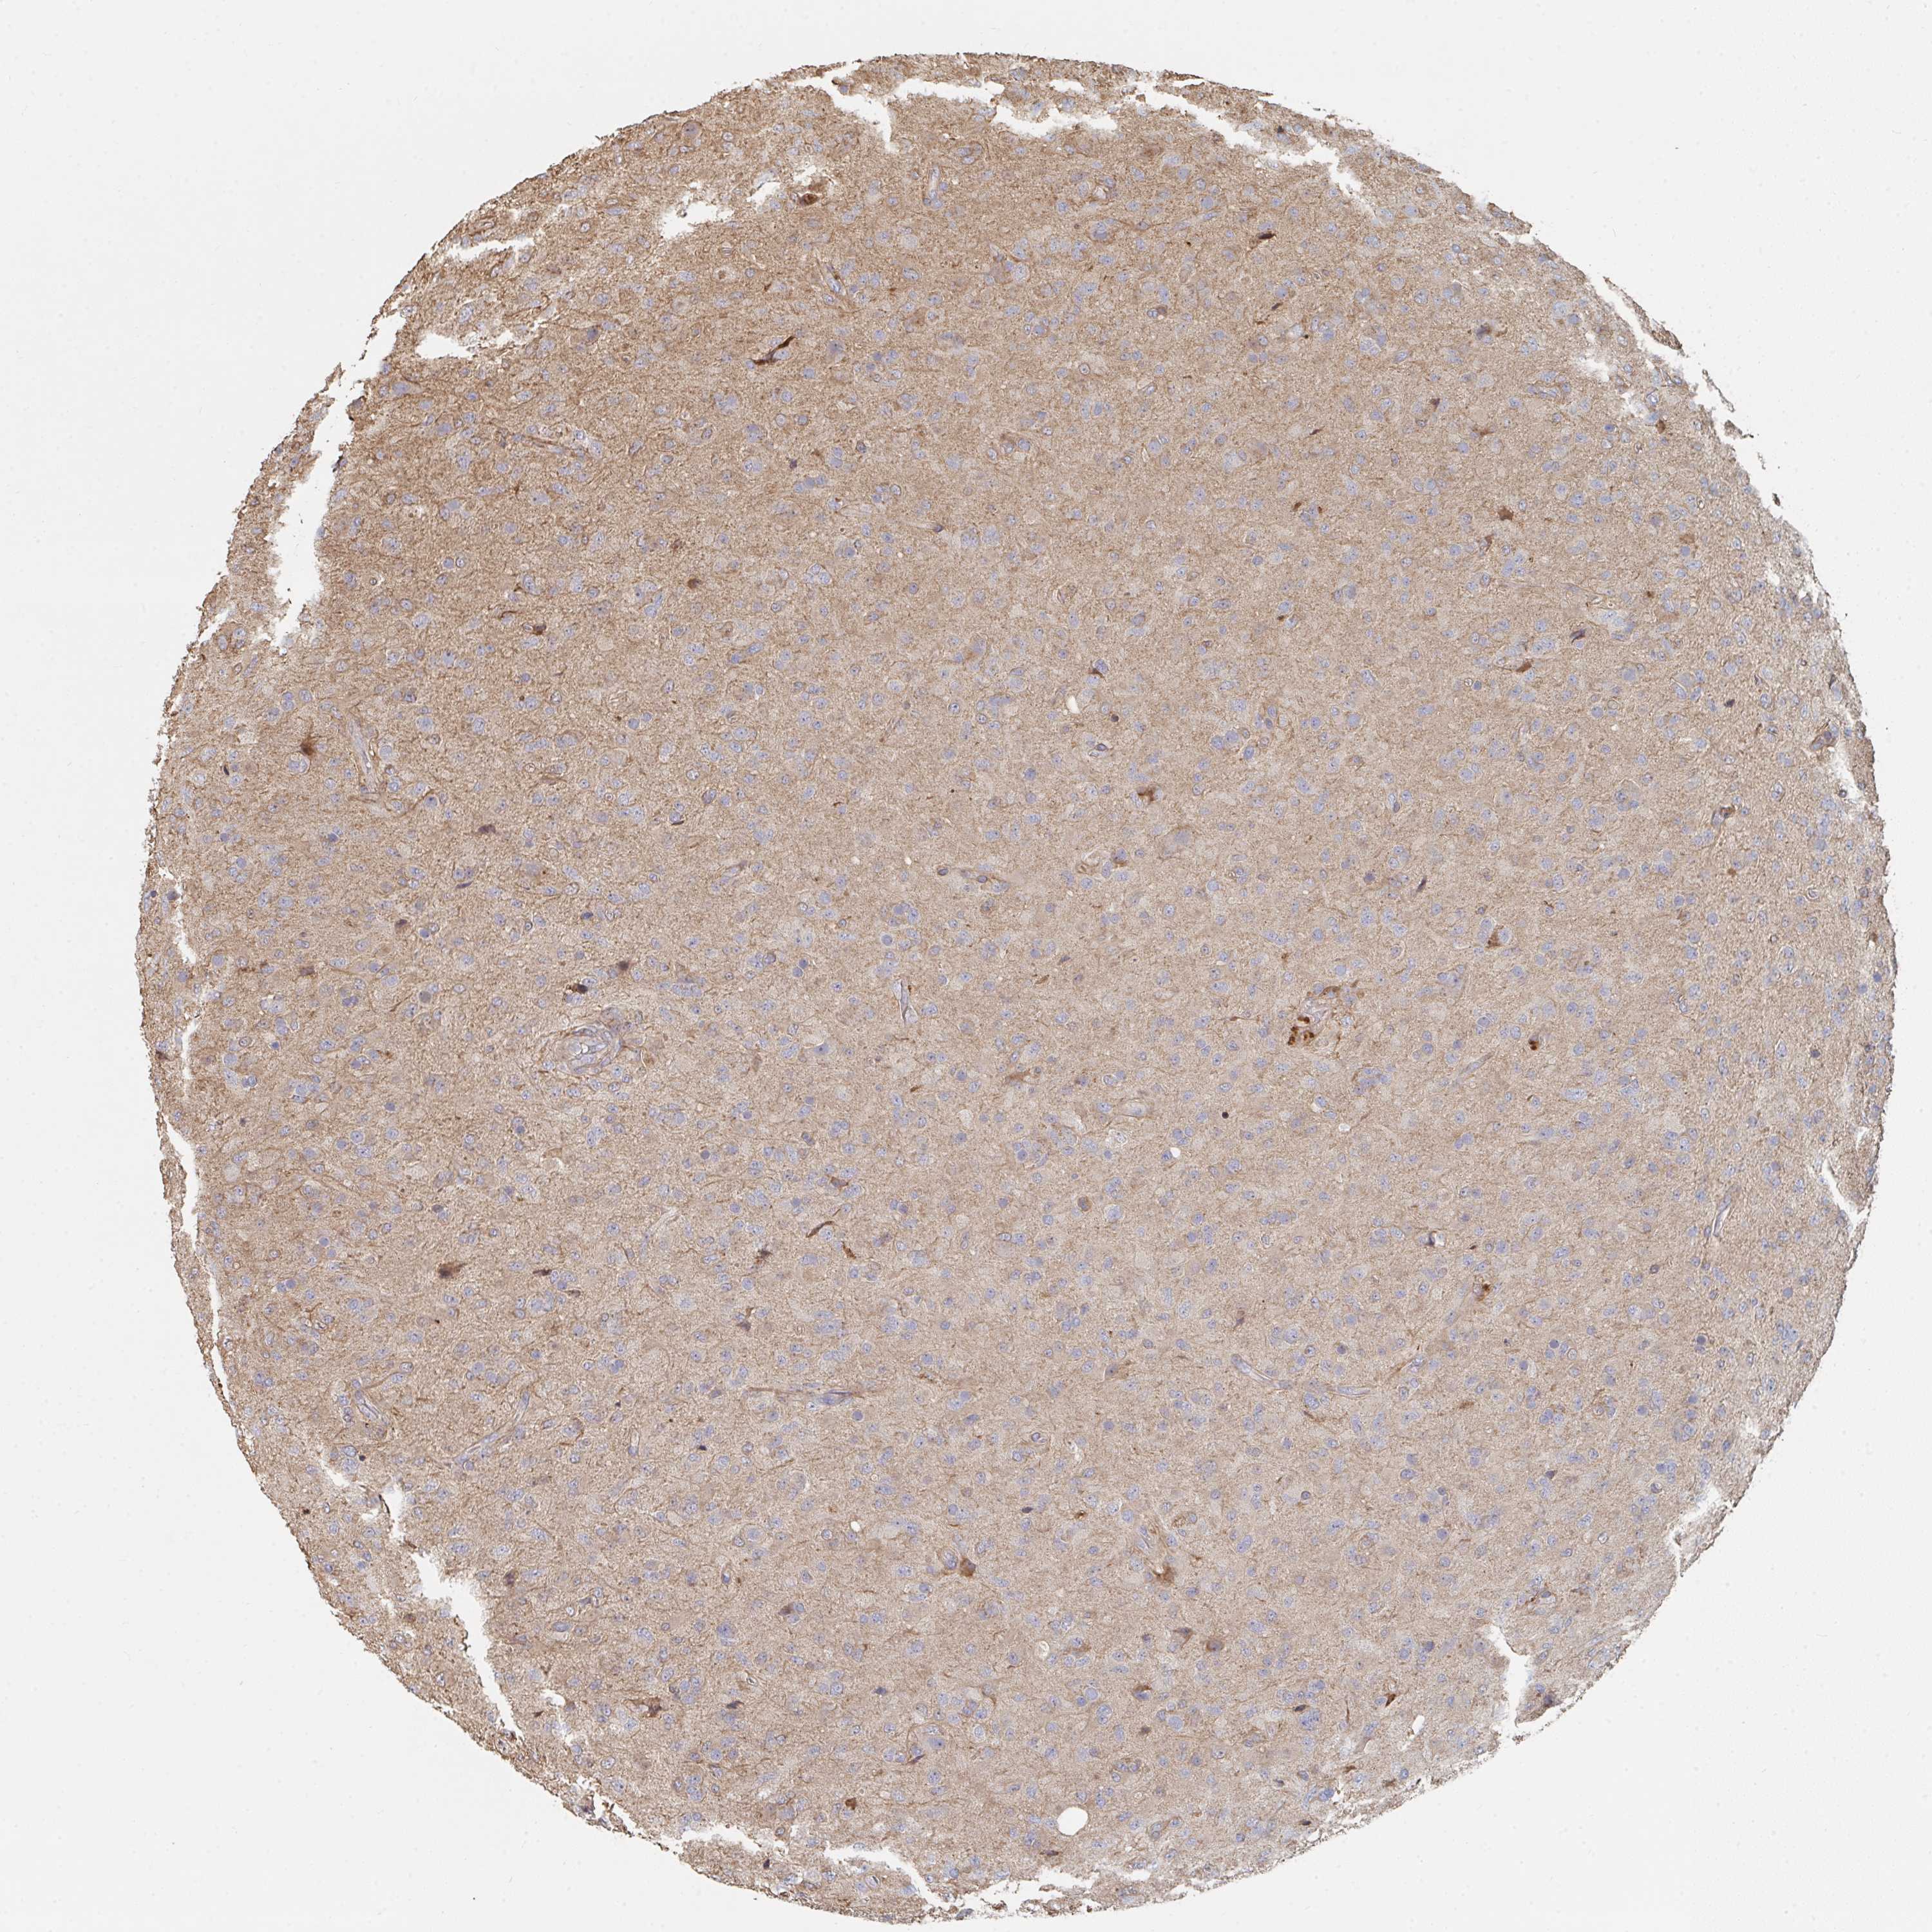

GLIOMA - Protein expressioni

A mouse-over function shows sample information and annotation data. Click on an image to view it in a full screen mode. Samples can be filtered based on level of antibody staining by selecting one or several of the following categories: high, medium, low and not detected. The assay and annotation is described here.

Note that samples used for immunohistochemistry by the Human Protein Atlas do not correspond to samples in the TCGA dataset.

Antibody stainingi

Antibody staining in the annotated cell types in the current human tissue is reported as not detected, low, medium, or high, based on conventional immunohistochemistry profiling in selected tissues. This score is based on the combination of the staining intensity and fraction of stained cells.

Each image is clickable and will lead to virtual microscopy that enables deeper exploration of all samples and also displays staining intensity scores, fraction scores and subcellular localization as well as patient and tissue information for each sample.

Antibody HPA031335

Antibody CAB004076

Antibody CAB080153

Antibody CAB080157

Glioma, malignant, Low grade

Glioma, malignant, High grade

Glioma, malignant, NOS